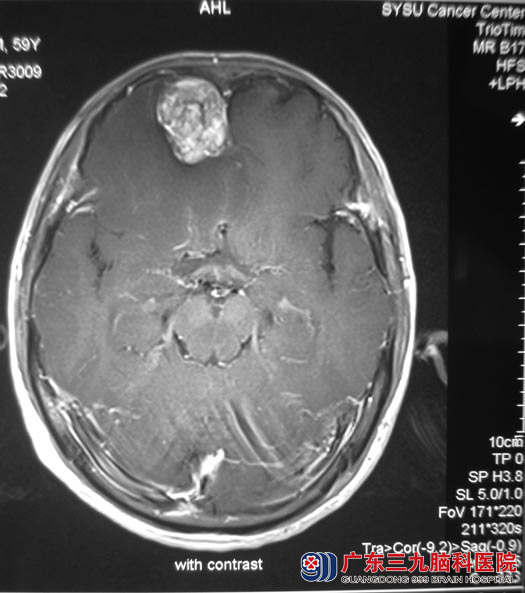

广东三九脑科医院进一步头颅MR检查提示:右侧额叶占位,大小约3cm×3cm,考虑脑膜瘤可能性大。

9月1日,由综合神经外科 鲁明主任主刀,在全麻下行右侧额部脑膜瘤切除术,术中显微镜下见脑组织受压,肿瘤位于右额底,紧邻矢状窦,肿瘤呈红白色,质地硬,血运一般,与脑组织边界较清,在镜下予肿瘤全切,手术顺利。一周后王先生即康复出院。术后病理结果为:过渡型脑膜瘤(WHO I级)。